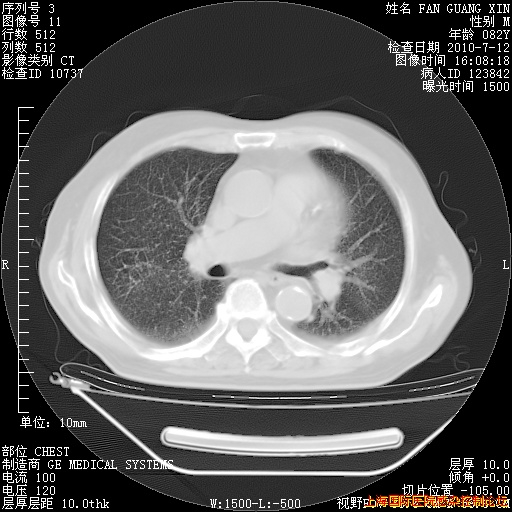

6月12日纵膈窗

今天复查CT

整整相隔30天的肺部CT好像有所好转啊。甲强龙减量第3天,需要观察体温。